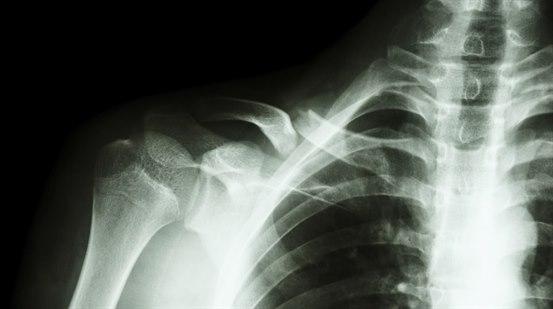

Se tegning av normalt skulderskjelett:

Røntgen bekrefter diagnosen. Noen ganger er det aktuelt med kontrollbilde. Ved greenstick-brudd holder det som regel med det ene bildet.